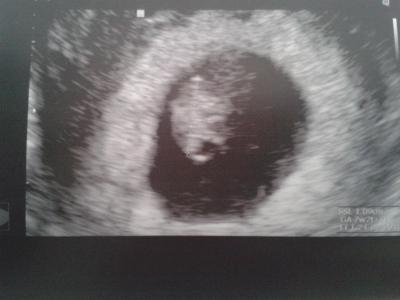

Hallo Mädels, ich habe Gott sei Dank gute Nachrichten. Heute an 7+0 ist mein Kügelchen 1,09 cm groß und das Herz schlägt schön. Mein FA war sehr zufrieden. Wegen meiner Beschwerden hat er mich zwei Wochen krankgeschrieben. Am 16.1. habe ich den nächsten Termin, dann bekomme ich endlich auch den Mutterpass mit (heute ging noch nicht, da sie heute erst Blut genommen haben und deswegen die Aufkleber noch fehlen). Hier noch ein Bildchen von "Kügelchen" LG

Bild zu Kügelchen gehts gut, so erleichtert - Forum für August - Mamis